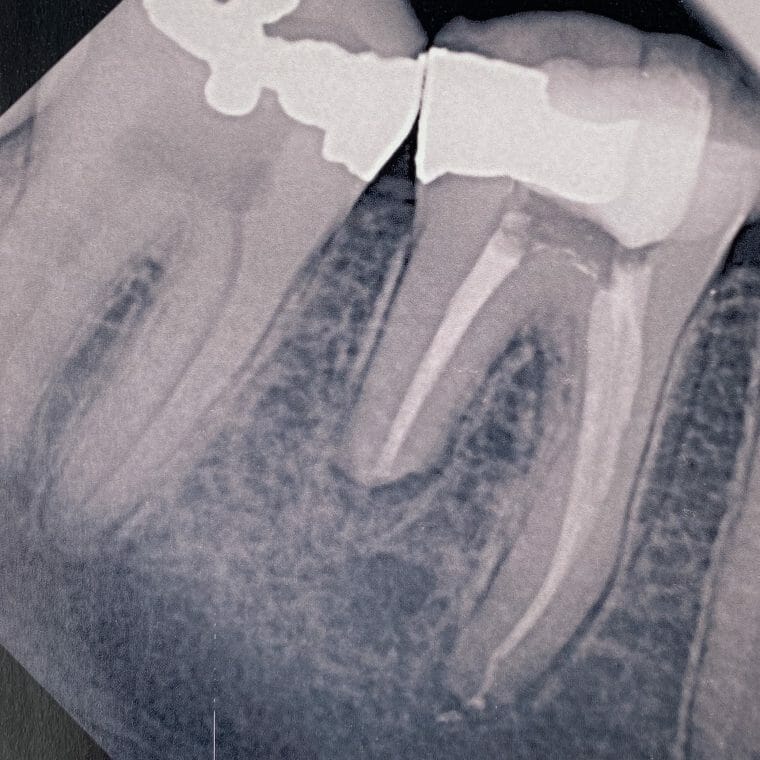

Internal Bleaching

Case Studies/